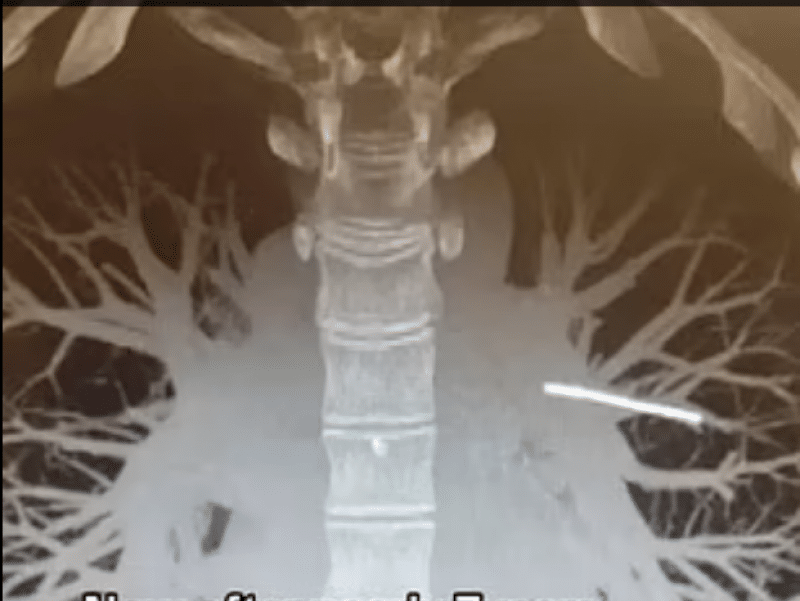

Rebecca Hardy, în vârstă de 29 de ani, s-a prezentat la consultație pentru a-și scoate implantul contraceptiv, pe care îl avea în brațul stâng de trei ani. Cu toate acestea, medicii nu au putut localiza dispozitivul. După o căutare laborioasă, acesta a fost găsit într-una dintre arterele pulmonare, o zonă critică pentru circulația sângelui între inimă și plămâni. Perspectiva îndepărtării implantului a stârnit îngrijorare în rândul medicilor, deoarece exista riscul ca acesta să rupă o arteră în timpul procedurii. Având în vedere aceste riscuri, Rebecca Hardy a fost sfătuită să lase implantul în locul său actual, potrivit Daily Mail.

Implantul contraceptiv Nexplanon, de dimensiunea unui chibrit, este conceput pentru a elibera treptat progestogen în corp pentru a preveni sarcina. Cu toate acestea, în cazul doamnei Hardy, dispozitivul a migrat în mod neașteptat în arterele pulmonare. Implanturile contraceptive sunt utilizate pe scară largă și sunt considerate sigure și eficiente. Cu toate acestea, cazurile rare de migrare pot ridica întrebări cu privire la siguranța și gestionarea acestor dispozitive. Dispozitivul contraceptiv, cât un băț de chibrit, a migrat din braț